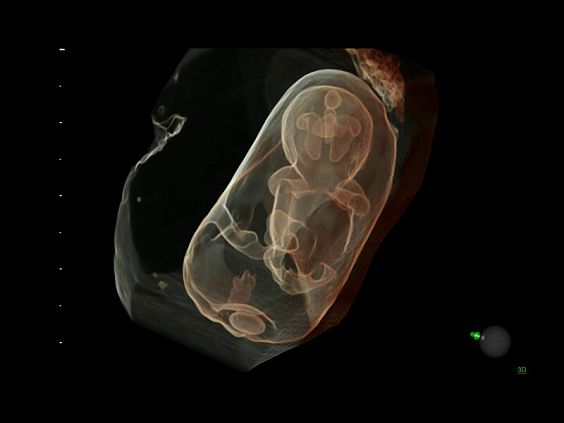

• HDlive Silhouette - режим "Силуэт" с подчеркиванием границ тканей и объектов, "объем в объеме"

• Технология HDlive Silhouette — задает разный уровень прозрачности, помогая выявлять контуры внутренних структур и точнее оценивать состояние плода в первом триместре.

• Программа 3D и режим инверсии (при наличии специализированных датчиков)